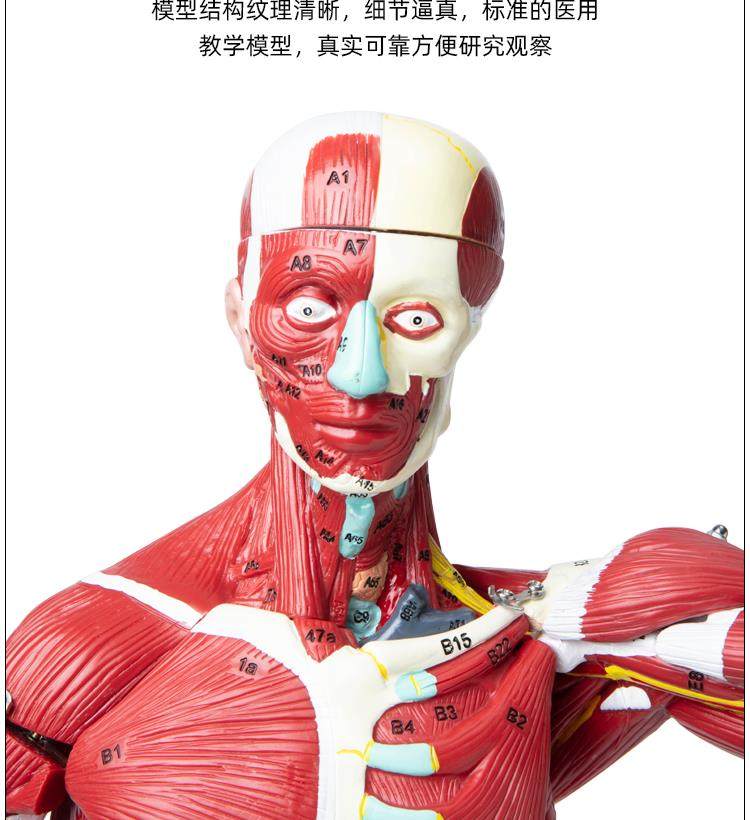

Human Body Muscle Internal Organ Disassembly Anatomy Structure Model Tissue Exercise Artificial Medical Teaching Aids

| Color Classification | 85 Human Muscle Internal Organs Removable Organ,50cm Muscle Model |